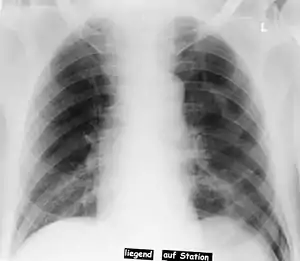

Deep sulcus sign

In radiology, the deep sulcus sign on a supine chest radiograph is an indirect indicator of a pneumothorax.[1][2] In a supine film, it appears as a deep, lucent, ipsilateral costophrenic angle[3] within the nondependent portions of the pleural space as opposed to the apex (of the lung) when the patient is upright. The costophrenic angle is abnormally deepened when the pleural air collects laterally, producing the deep sulcus sign.[4]

| Pneumothorax left sided | |

| Differential diagnosis | pneumothorax |